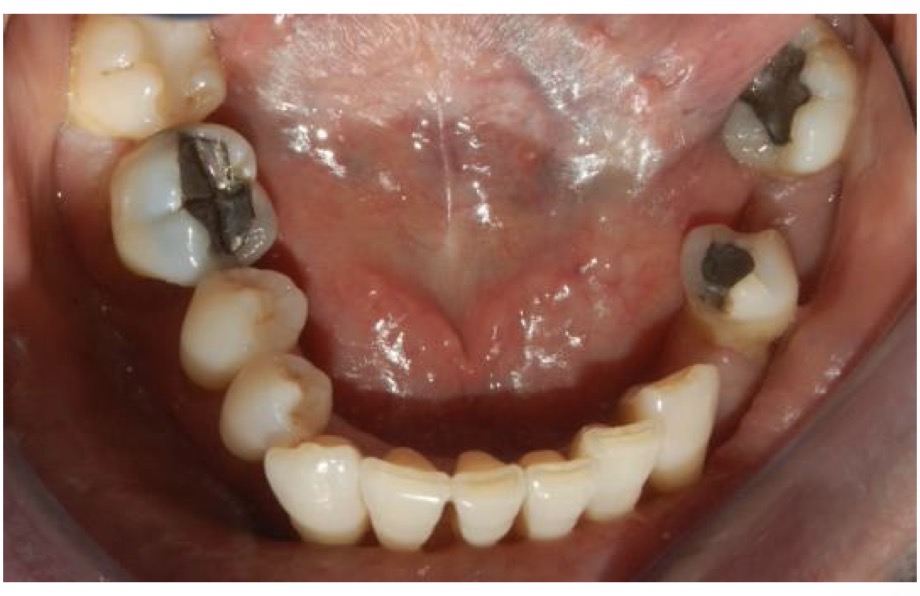

CHẨN ĐOÁN ?

SÂU RĂNG SAU XẠ TRỊ( sâu nhiều răng và lang quanh cổ răng)